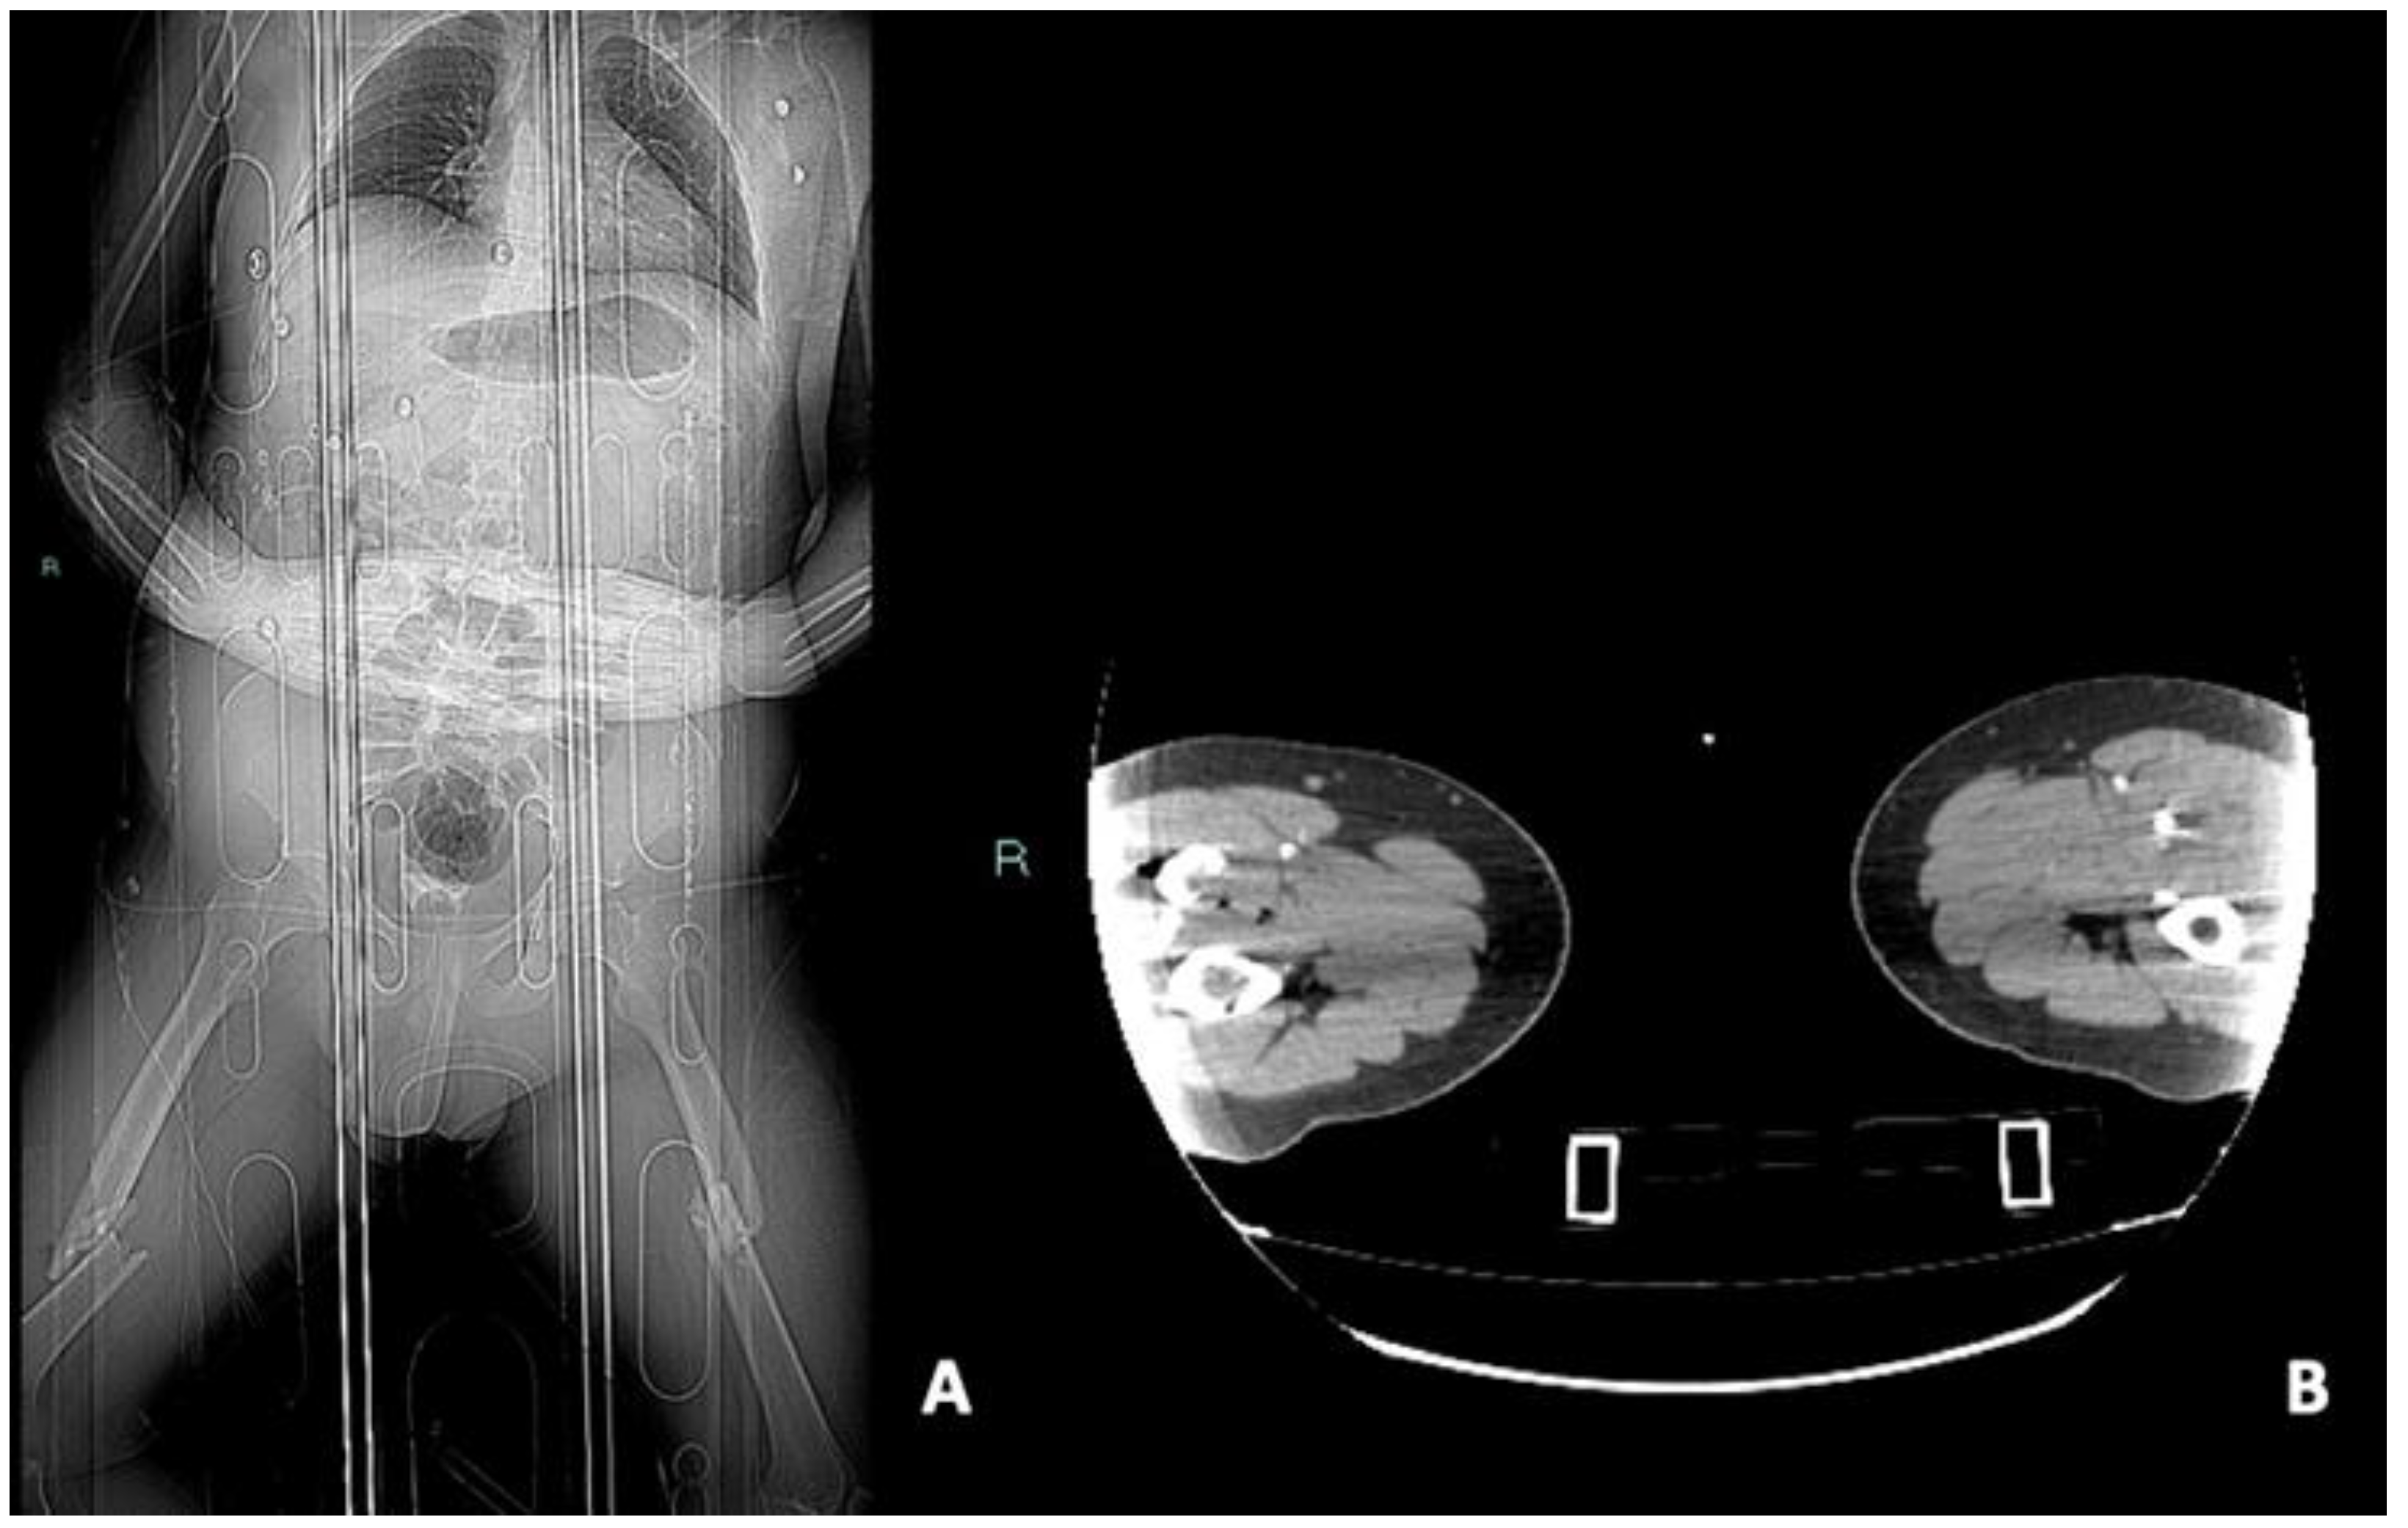

3.2. CTA Imaging Findings

- Gakhal, M.S.; Sartip, K.A. CT angiography signs of lower extremity vascular trauma. AJR Am. J. Roentgenol. 2009, 193, W49–W57. [Google Scholar] [CrossRef] [PubMed]

- Miller-Thomas, M.M.; West, O.C.; Cohen, A.M. Diagnosing traumatic arterial injury in the extremities with CT angiography: Pearls and pitfalls. Radiographics 2005, 25 (Suppl. S1), S133–S142. [Google Scholar] [CrossRef] [PubMed]

- Madhuripan, N.; Mehta, P.; Smolinski, S.E.; Njuguna, N. Computed Tomography Angiography of the Extremities in Emergencies. Semin. Ultrasound CT MR 2017, 38, 357–369. [Google Scholar] [CrossRef] [PubMed]